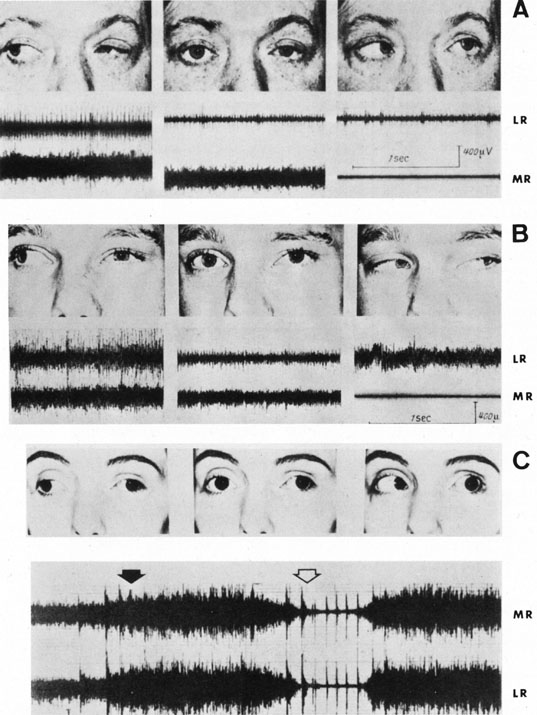

ocular torticollis. J Pediatr Ophthalmol 30:8, 1993 257. Rubin SE, Wagner RS: Ocular torticollis. Surv Ophthalmol 30:366, 1986 258. Catalano RA, Simon JW, Krohel GB, et al: Functional visual loss in children. Ophthalmology 93:385, 1986 259. Jacobson AM, de Groot M: Psychology of visual loss. In Principles and Practice of Ophthalmology. Philadelphia: WB Saunders |